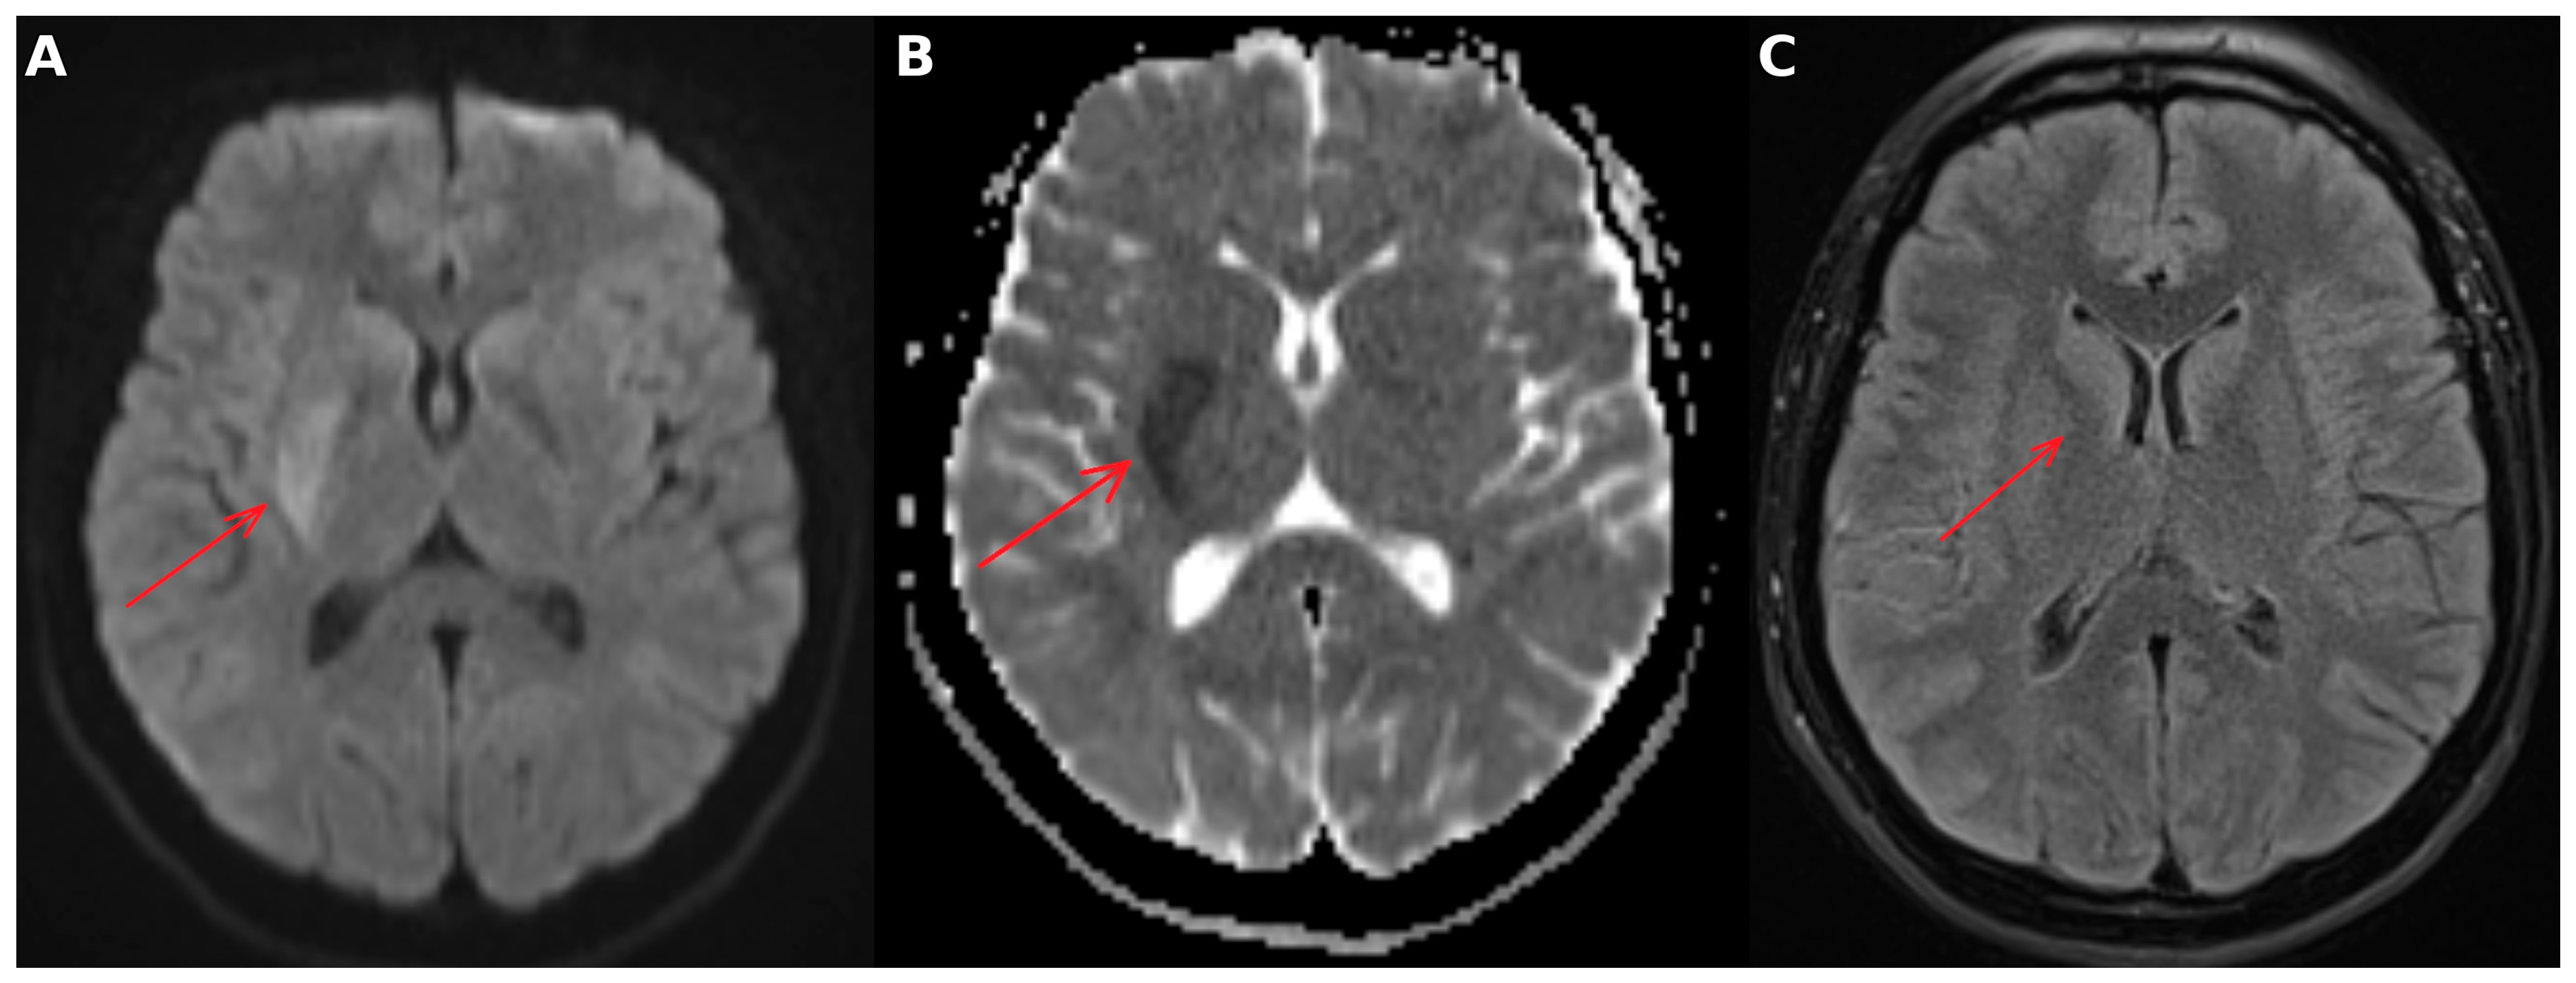

4. Follow-Up